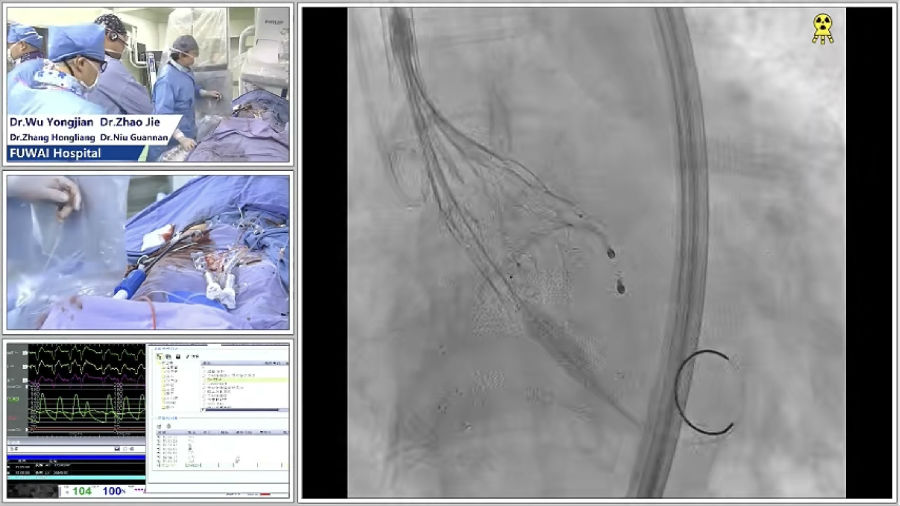

学术会议手术转播